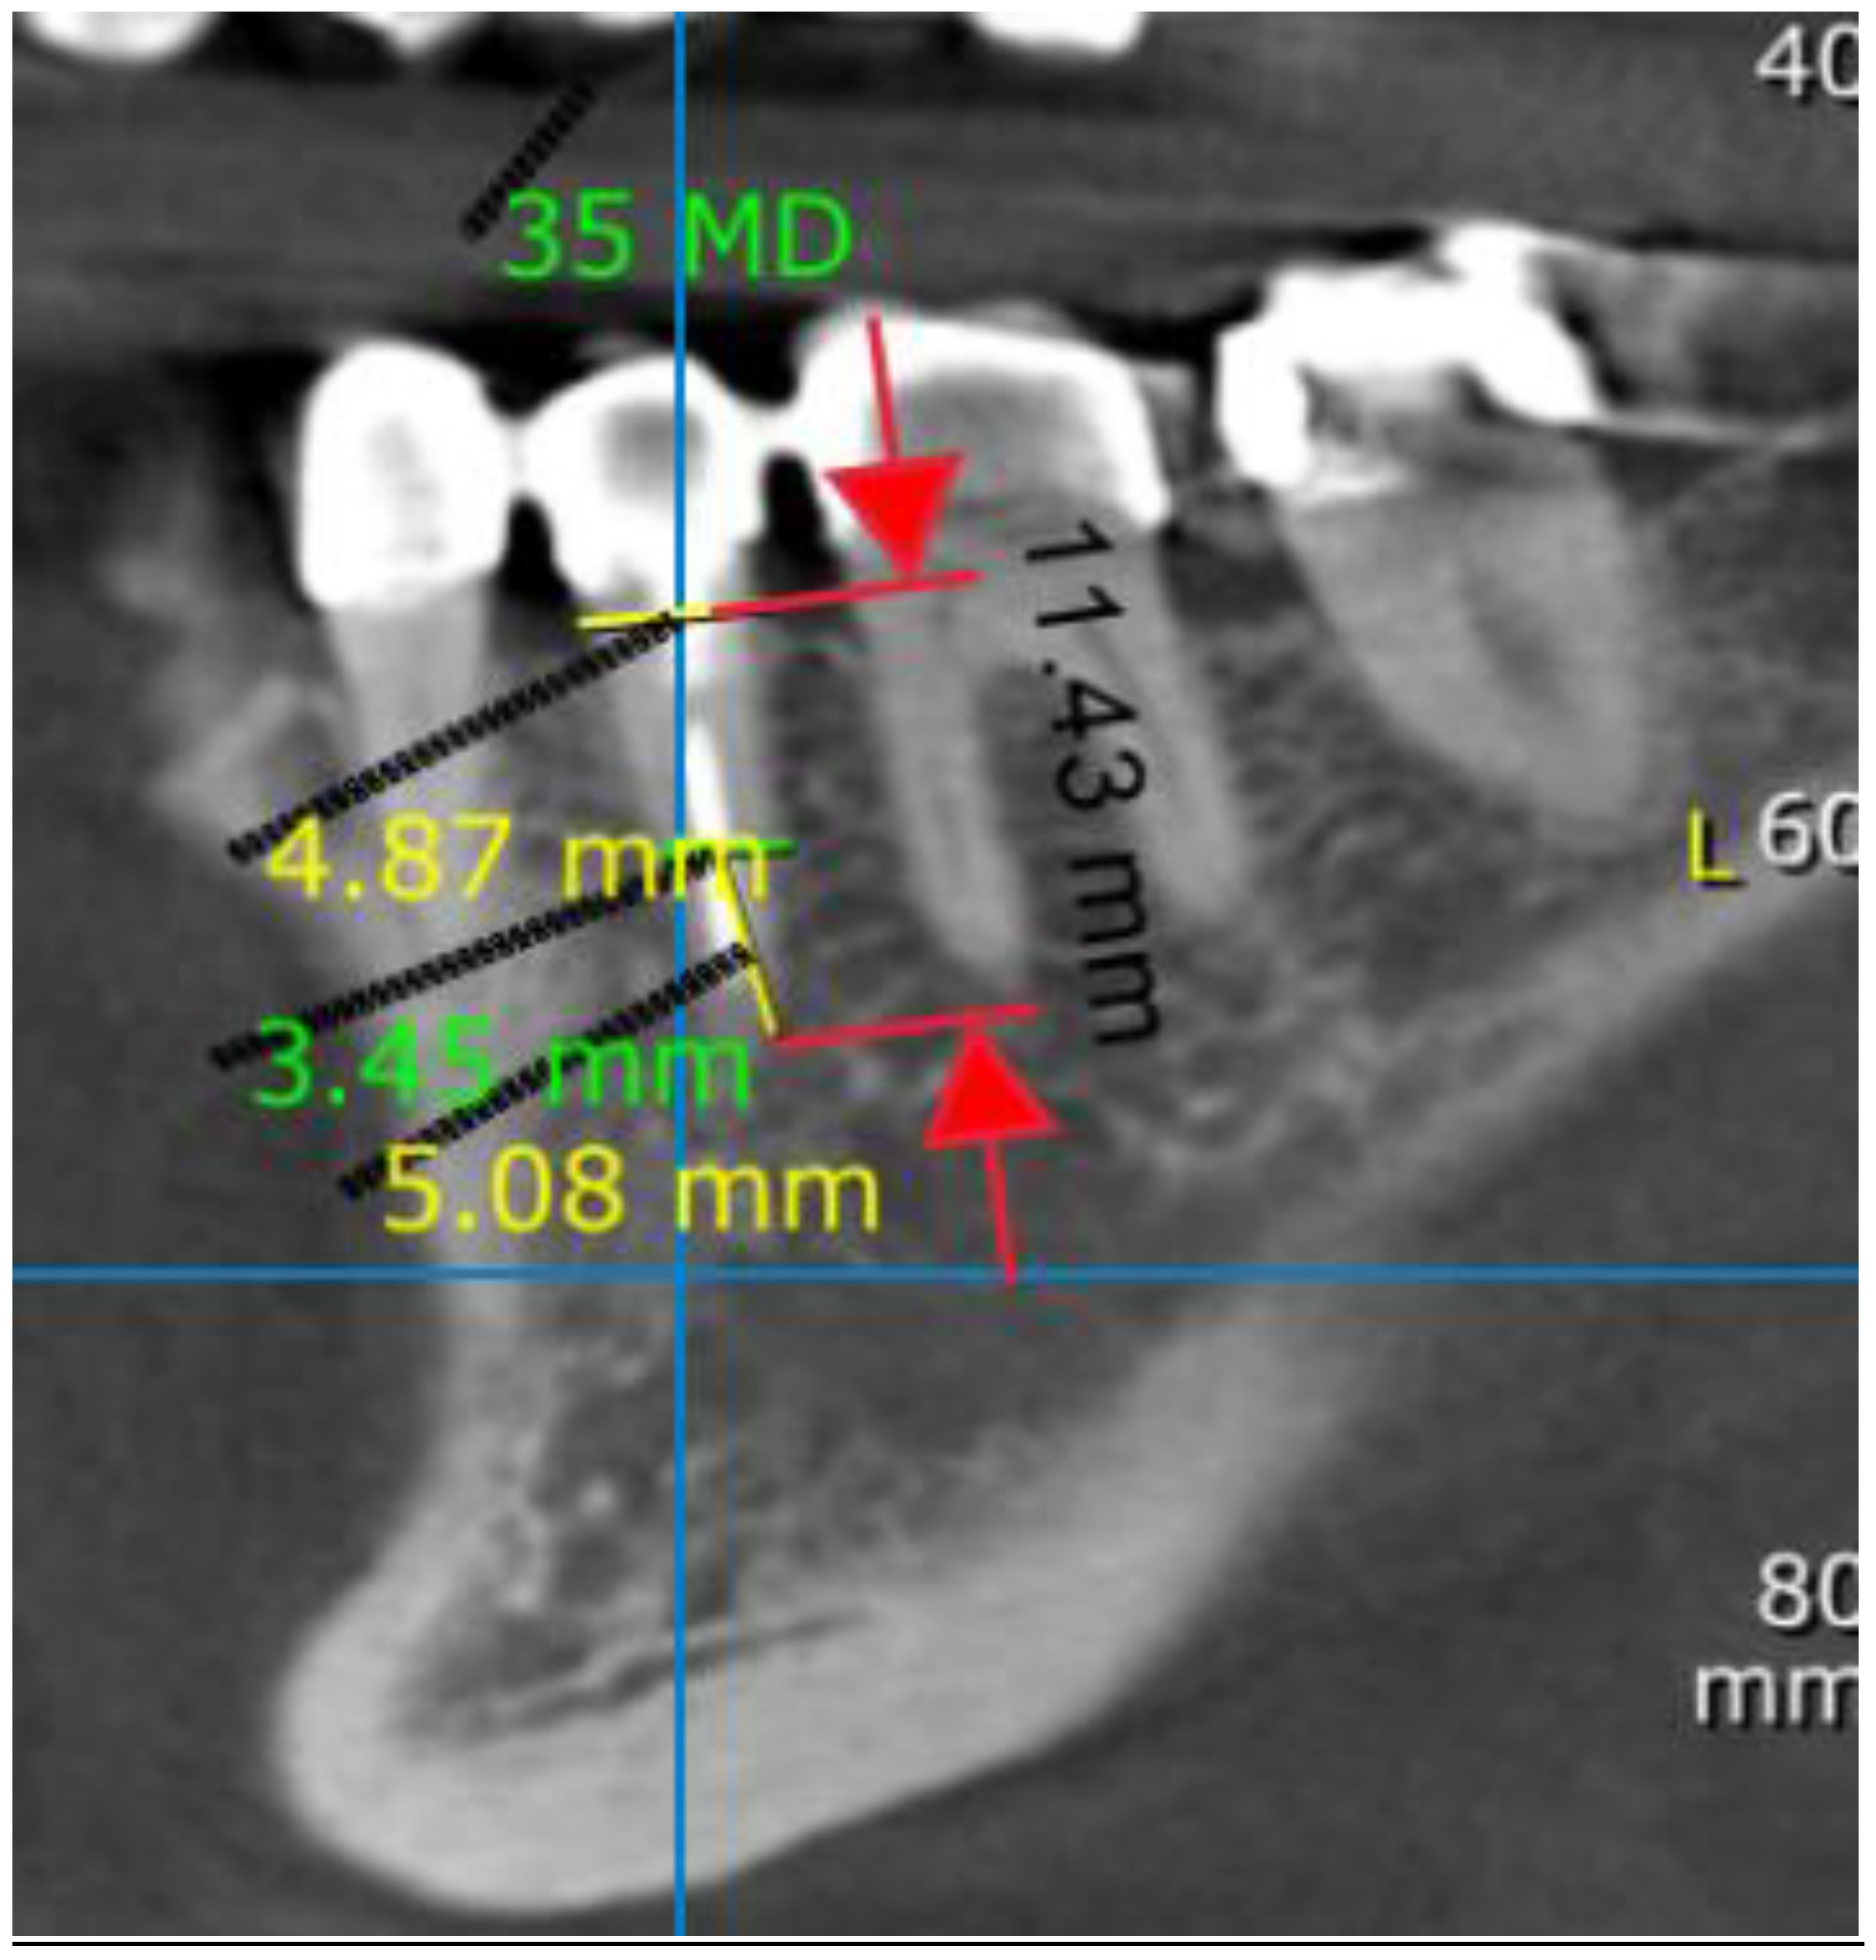

2.3. Measurements

3.2.1. Mesiodistal Aspect

3.2.2. Vertical Aspect